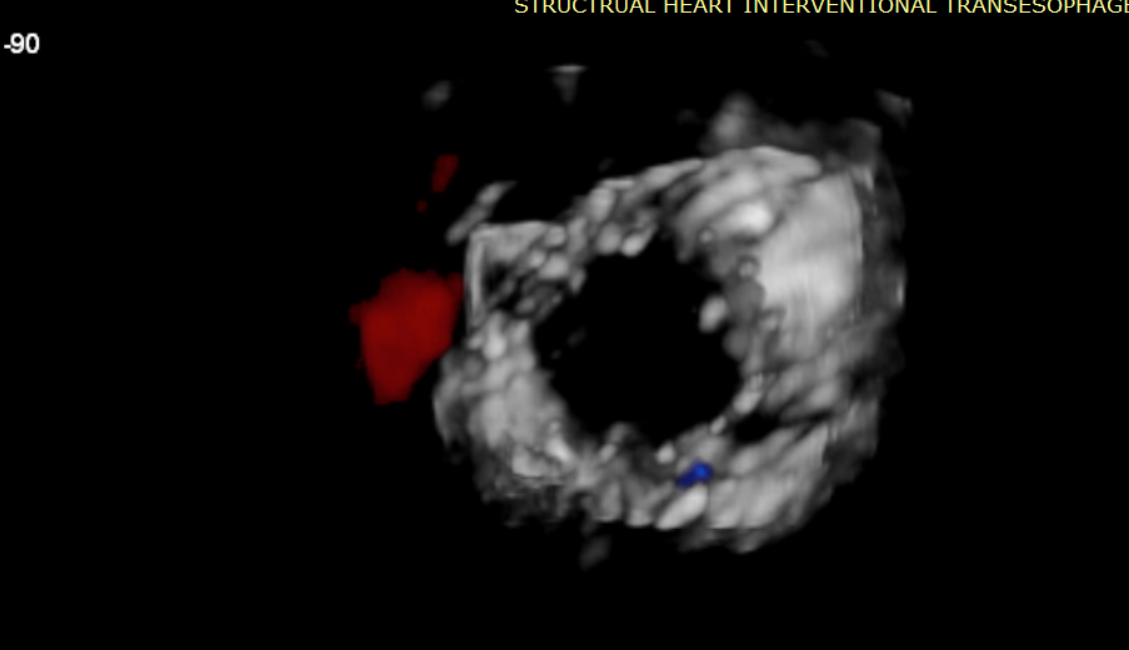

術前超聲提示大量三尖瓣反流

術中輸送器在超聲引導下調整位置

術后超聲提示僅殘余輕微瓣周漏